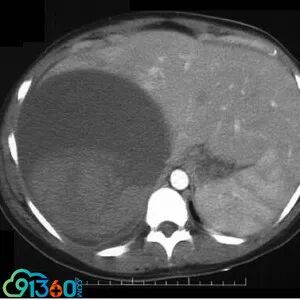

一般病史:怀孕35周,超声检查发现右上腹有一个囊腔。开始认为是肝囊肿。病人有明显的右上腹疼痛,遂在超声指导下抽吸约2000ml的血性液体。但病人随后发生头晕和直立性低血压。重复超声检查发现囊腔内重新集聚液体符合囊肿内出血。遂进行诱导分娩,行CT检测发现右肾上腺囊肿。然后进行囊肿引流和手术切除。

病理诊断:血管性肾上腺囊肿。

肾上腺囊肿少见,一般可分为上皮性、寄生性和血管型。血管性肾上腺囊肿是目前最常见的类型,传统上被亚分为内皮性和出血性(假性囊肿)亚型。尽管它们有不同的组织学特征,最近的研究显示这两个疾病实体或许代表着血管肾上腺病变的谱系。

血管肾上腺囊肿大小不一,从镜下可见到最大直径50cm,可含有至多11升液体。左右侧发病相当,双侧发病率约8%。所有年龄均可发病,发病高峰为50-60岁,男女之比为2:1。血管性肾上腺囊肿的症状通常伴有大的囊肿,推测可能是由于挤压紧邻的内脏,包括疼痛和胃肠道不适。